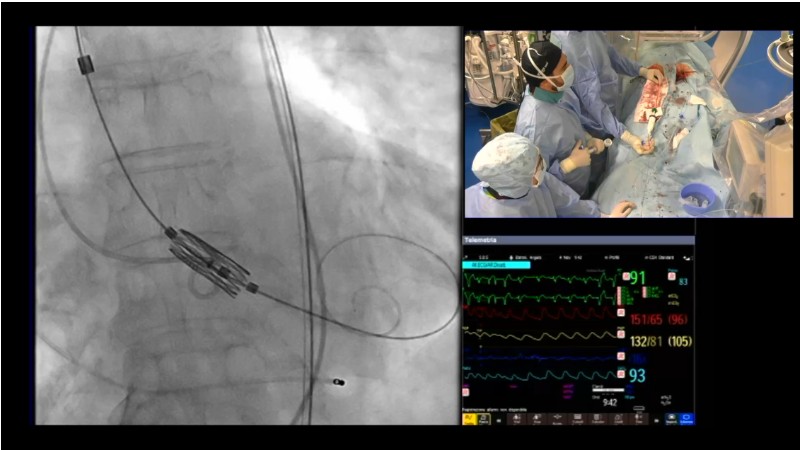

Discover the latest insights from the Myval THV series in this session from PCR London Valves 2025. Through real-world, case-based learning, the session explores lifetime management strategies for TAVI patients, the clinical relevance of intermediate and extra-large valve sizing, and the impact of foreshortening on accurate valve deployment.

Key presentations cover matching prostheses to patient anatomy, the importance of predictable valve performance in challenging situations, and pivotal trial data supporting Myval THV outcomes. Highlights include the OCTAPRO+ THV’s progressive design enabling precise deployment, the OctaAlign technique for commissural alignment, and next-generation strategies to optimize lifetime TAVI management.